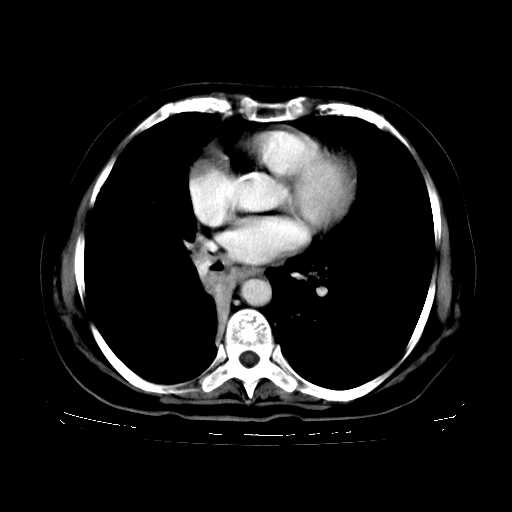

女,70岁,咳嗽、咳痰一个月,低热一周。

1.左上肺结核,部分纤维化。右肺中下叶部分肺不张,内见液化、坏死及点状钙化,右中下叶支气管壁增厚、管腔狭窄,见多个点状钙化,结合临床考虑支气管内膜结核,建议痰检查抗酸杆菌并参考血沉。两肺多个小圆点状高密度灶,境界模糊,多考虑结核肺内播散。但本人年龄较大首先应支气管镜检以除外右肺癌。

2.胸主动脉夹层。

支持,首先一元论解释。胸主动脉部分层面环形低密度,中心强化。环形影不强化。不象真假腔的改变。我考虑动脉炎,不太支持夹层动脉瘤-和大家的观点不一致,希望楼主让患者再做个心血管的彩超吧。